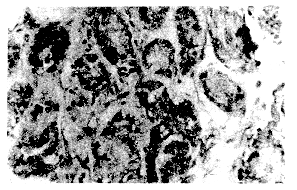

二、两种抗原在胃粘膜中的定位与分布

HCV NS3、NS5的阳性物质主要位于胃粘膜上皮腺体细胞的胞浆中,阳性细胞呈单个、散在或片灶状分布(见图1、2)。两种抗原在胃粘膜中的检出率分别为33.33%和27.27%,经统计学处理差异无显著性(χ2=0.48,P>0.05)。此外,部分病例的淋巴细胞的胞浆中也可见到两种抗原。

图1 HCV NS3阳性胃粘膜体细胞(胞浆呈深色)

免疫组化×200

图2 HCV NS5阳性物质在胃腺体细胞胞浆内表达

免疫组化×400